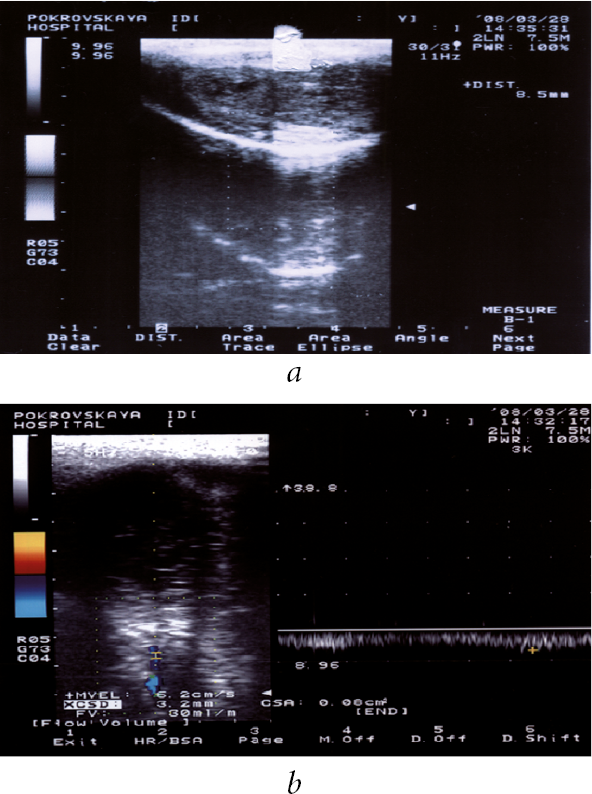

Patients in both groups were simultaneously treated with magnetic-laser therapy by using the AMVL-01 device, which creates an LNP at 2 atm in the flask and causes an erection with 10–20 min duration (Figure 1). The LNP therapy included 10 procedures. In severe erectile dysfunction, a PDE5 inhibitor was prescribed in individually selected doses. The results of treatment were evaluated 6 and 12 months after its onset.

Fig. 1. Diagnosis of curvature of the penis on the apparatus AMVL-01 (apparatus vacuum-laser therapeutic urological) in patient A., 54 years old, with Peyronie's disease. Local negative pressure with maximum discharge in the flask affects the baro-and thermoreceptors of the skin of the penis, enhances microcirculation in its vessels. An insignificant curvature (angle of curvature - 30 degrees) of the penis